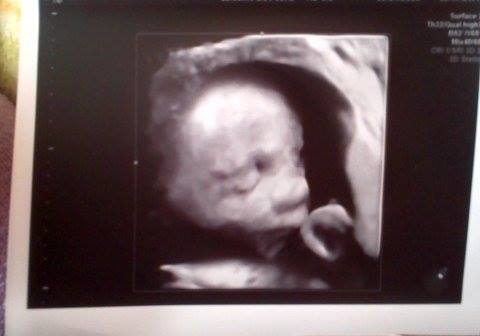

Moja Tosieńka:)

• tosia-21tyg-01.jpg

tosia-21tyg-01.jpg

200,4 KB · Wyświetleń: 127